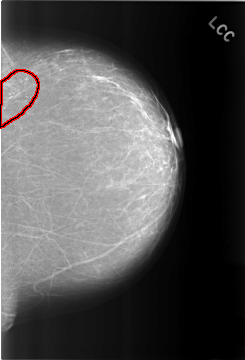

FILE: C_0317_1.LEFT_CC.OVERLAY

TOTAL_ABNORMALITIES 1

ABNORMALITY 1

LESION_TYPE CALCIFICATION TYPE PLEOMORPHIC DISTRIBUTION CLUSTERED

ASSESSMENT 4

SUBTLETY 5

PATHOLOGY BENIGN

TOTAL_OUTLINES 1

BOUNDARY